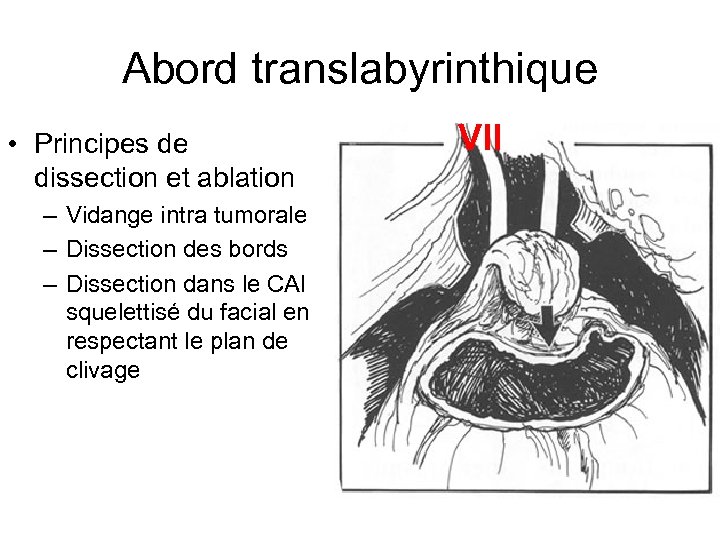

Abord translabyrinthique • Principes de dissection et ablation – Vidange intra tumorale – Dissection des bords – Dissection dans le CAI squelettisé du facial en respectant le plan de clivage VII

Abord translabyrinthique • Principes de dissection et ablation – Vidange intra tumorale – Dissection des bords – Dissection dans le CAI squelettisé du facial en respectant le plan de clivage VII